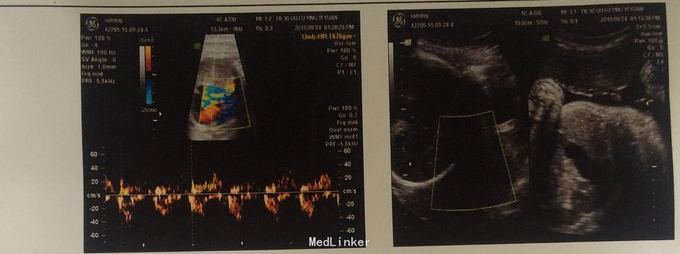

患者停经9个月余,胎动4个月余。腹软,

宫高36厘米,腹围119厘米,消毒内诊,宫颈半消,宫口容一指,先露臀,S-3

孕1产0,妊娠39周,骶左前!术中麻醉由于患者肥胖,麻醉进针较吃力,术中麻醉顺利,术后患者自述右腿麻木,没有感觉!术后第三天恢复正常!